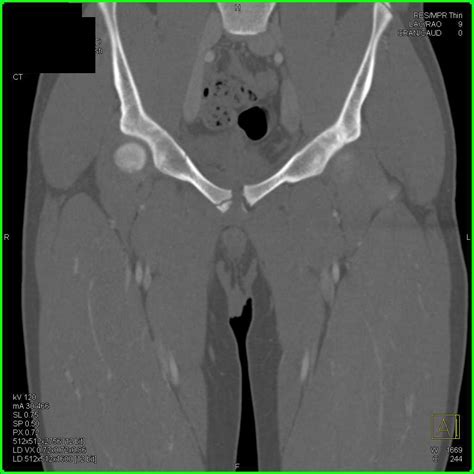

CT Scan Used for detailed cross-sectional views if the X-ray is unclear or if complex fractures are suspected.

• Inferior Pubic Ramus CT